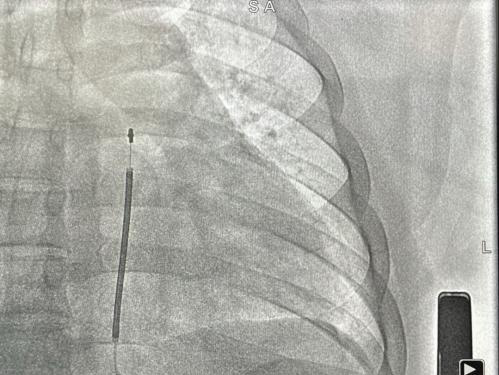

术后影像

手术在全麻醉下进行。常规消毒、铺巾,取左腋中线平等第5-6肋为预定点,切开一约5cm切口,逐层分离至皮下,分离囊袋至背阔肌与前锯肌之间。再次于胸骨柄右缘1cm为预定点,切开一长约3cm切口,逐层分离至深筋膜层,预埋两根缝合线用导引针,于切口间建立隧道,利用隧道针将电极沿皮下置入囊袋。再以切口位置建立隧道,同样以隧道针将导线头端沿深筋膜层,送至胸骨柄上缘(距切口14cm处),于切口处固定电极导线,囊袋处连接脉冲发生器(S-ICD A209),固定脉冲发生器于深筋膜层,排除空气后关闭深筋膜层。进行DFT测试,采用50HZ,200MA交流电方式进行诱颤,SICD正确识别,经首次65J除颤成功,除颤阻抗77欧姆。缝合皮肤,术区纱布覆盖,包扎,弹力绷带加压包扎止血。手术圆满成功,耗时约50分钟,术后第二天患者即可下床活动。